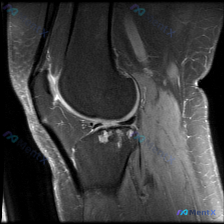

今天分享一份踝关节MRI的读片讨论,影像提示存在软骨异常,我们一起来梳理一下完整的分析思路。 病例影像基本信息 这是一份踝关节MRI冠状位T2加权图像,整理核心影像发现如下: 1. 骨骼系统:胫骨远端、距骨骨皮质连续性无中断,骨髓腔无明显弥漫性高信号,无明确急性骨髓水肿或骨挫伤 2. 关节与软骨:胫...